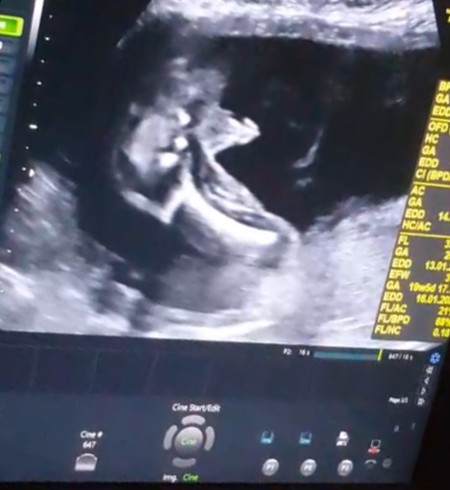

มีมั้ยค่ะ หมอบอกว่าลูกเป็นเพศชาย แต่พอใกล้ๆคลอดเปลี่ยนเป็นเพศหญิง ในรูปอย่างนี้มีโอกาสเป็นเพศหญิงมั้ยค่ะ